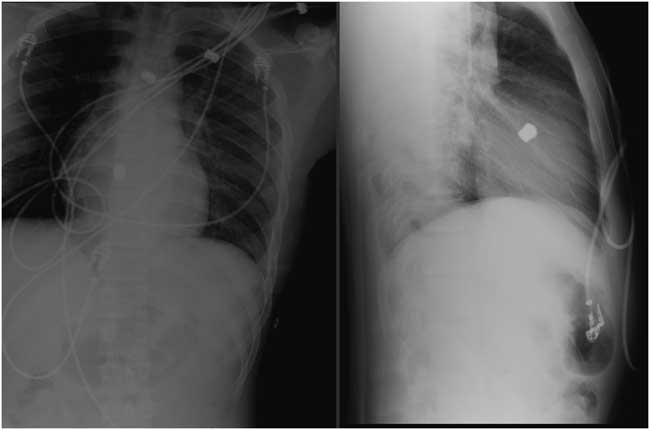

A 17-year-old man presented to the trauma resuscitation bay with a gunshot to the left flank, complaining only of chest tightness. A physical exam was notable for a heart rate of 72 beats/minute, blood pressure of 161/89 mm Hg, oxygen saturation of 100% on room air, and a single gunshot wound to the left thoracoabdomen in the anterior axillary line. Portable chest radiographs demonstrated a missile projecting over the middle of the heart (Figure 1). An emergent bedside echocardiogram noted normal biventricular function, no pericardial effusion, no hemothorax, and an immobile bullet lodged near the interventricular septum, with no color-flow Doppler evidence of septal defect. Initial labs showed a troponin I of 9.28 ng/dL. Given apparent hemodynamic stability, the patient did not proceed emergently to the operating room. A computed tomography angiography of the chest was performed and was most notable for splenic injury and a bullet within the interventricular septum with no hemothorax, pericardial effusion, or obvious cardiac injury. The patient underwent exploratory laparotomy notable for splenic injury leading to a splenectomy and repairs of injuries to the left lateral diaphragm and left lateral lobe of the liver. The following day, the patient returned to the operating room for median sternotomy and right atriotomy where the bullet was found lodged in the membranous septum beneath the septal leaflet of the tricuspid valve. There were no atrial or ventricular septal defects and no hemothorax. The bullet was removed, and a pericardial patch repair of the perimembranous bullet cavity was performed. A 2-cm×1.5-cm hole in the posterior left ventricular wall with adherent clot was also noted intraoperatively and repaired. The patient recovered in the surgical intensive care unit and was discharged home in excellent condition on hospital day 15.

Figure 1 Portable chest radiographs showing a bullet projecting over the middle of the heart.